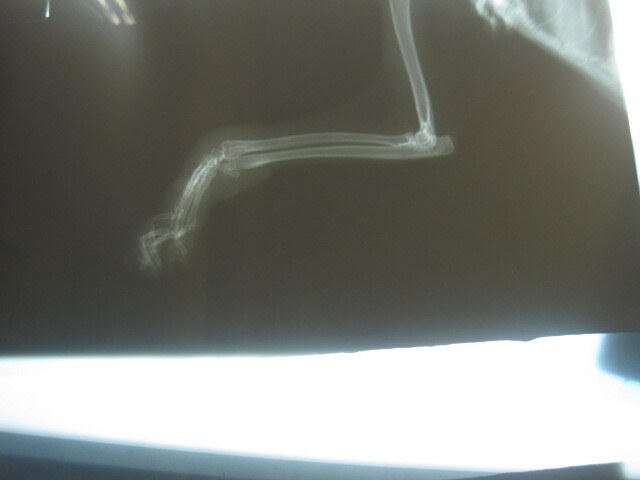

- 編號: 2622

主題: 左腕關節腫脹 有50元硬幣大的外傷 申請者姓名: 張慧敏 花色: 申請日期: 2013-06-20 16:27:53 申請者部落格: 申請者臉書網址: 所在縣市/合作醫院: 台北市/詠欣動物醫院 治療費用: 5700元 需求人數: 13人 已結案 (2013-08-06 14:28:47) 報名人員: davidlai(已付款)、Lynn、Liwing Lin(已付款)、Josephine(已付款)、Josephine(已付款)、Josephine(已付款)、Stephy An(已付款)、惠惠(已付款)、蔡餅乾(已付款)、Linda x4(已付款)、喵喵(已付款)、 候補人員: 黃安妮、RuRu Liu、 動物病情說明: 捕捉結紮發現左腕關節腫脹、有50元硬幣大的外傷,現已經復原R回,醫療費用還請各位幫忙